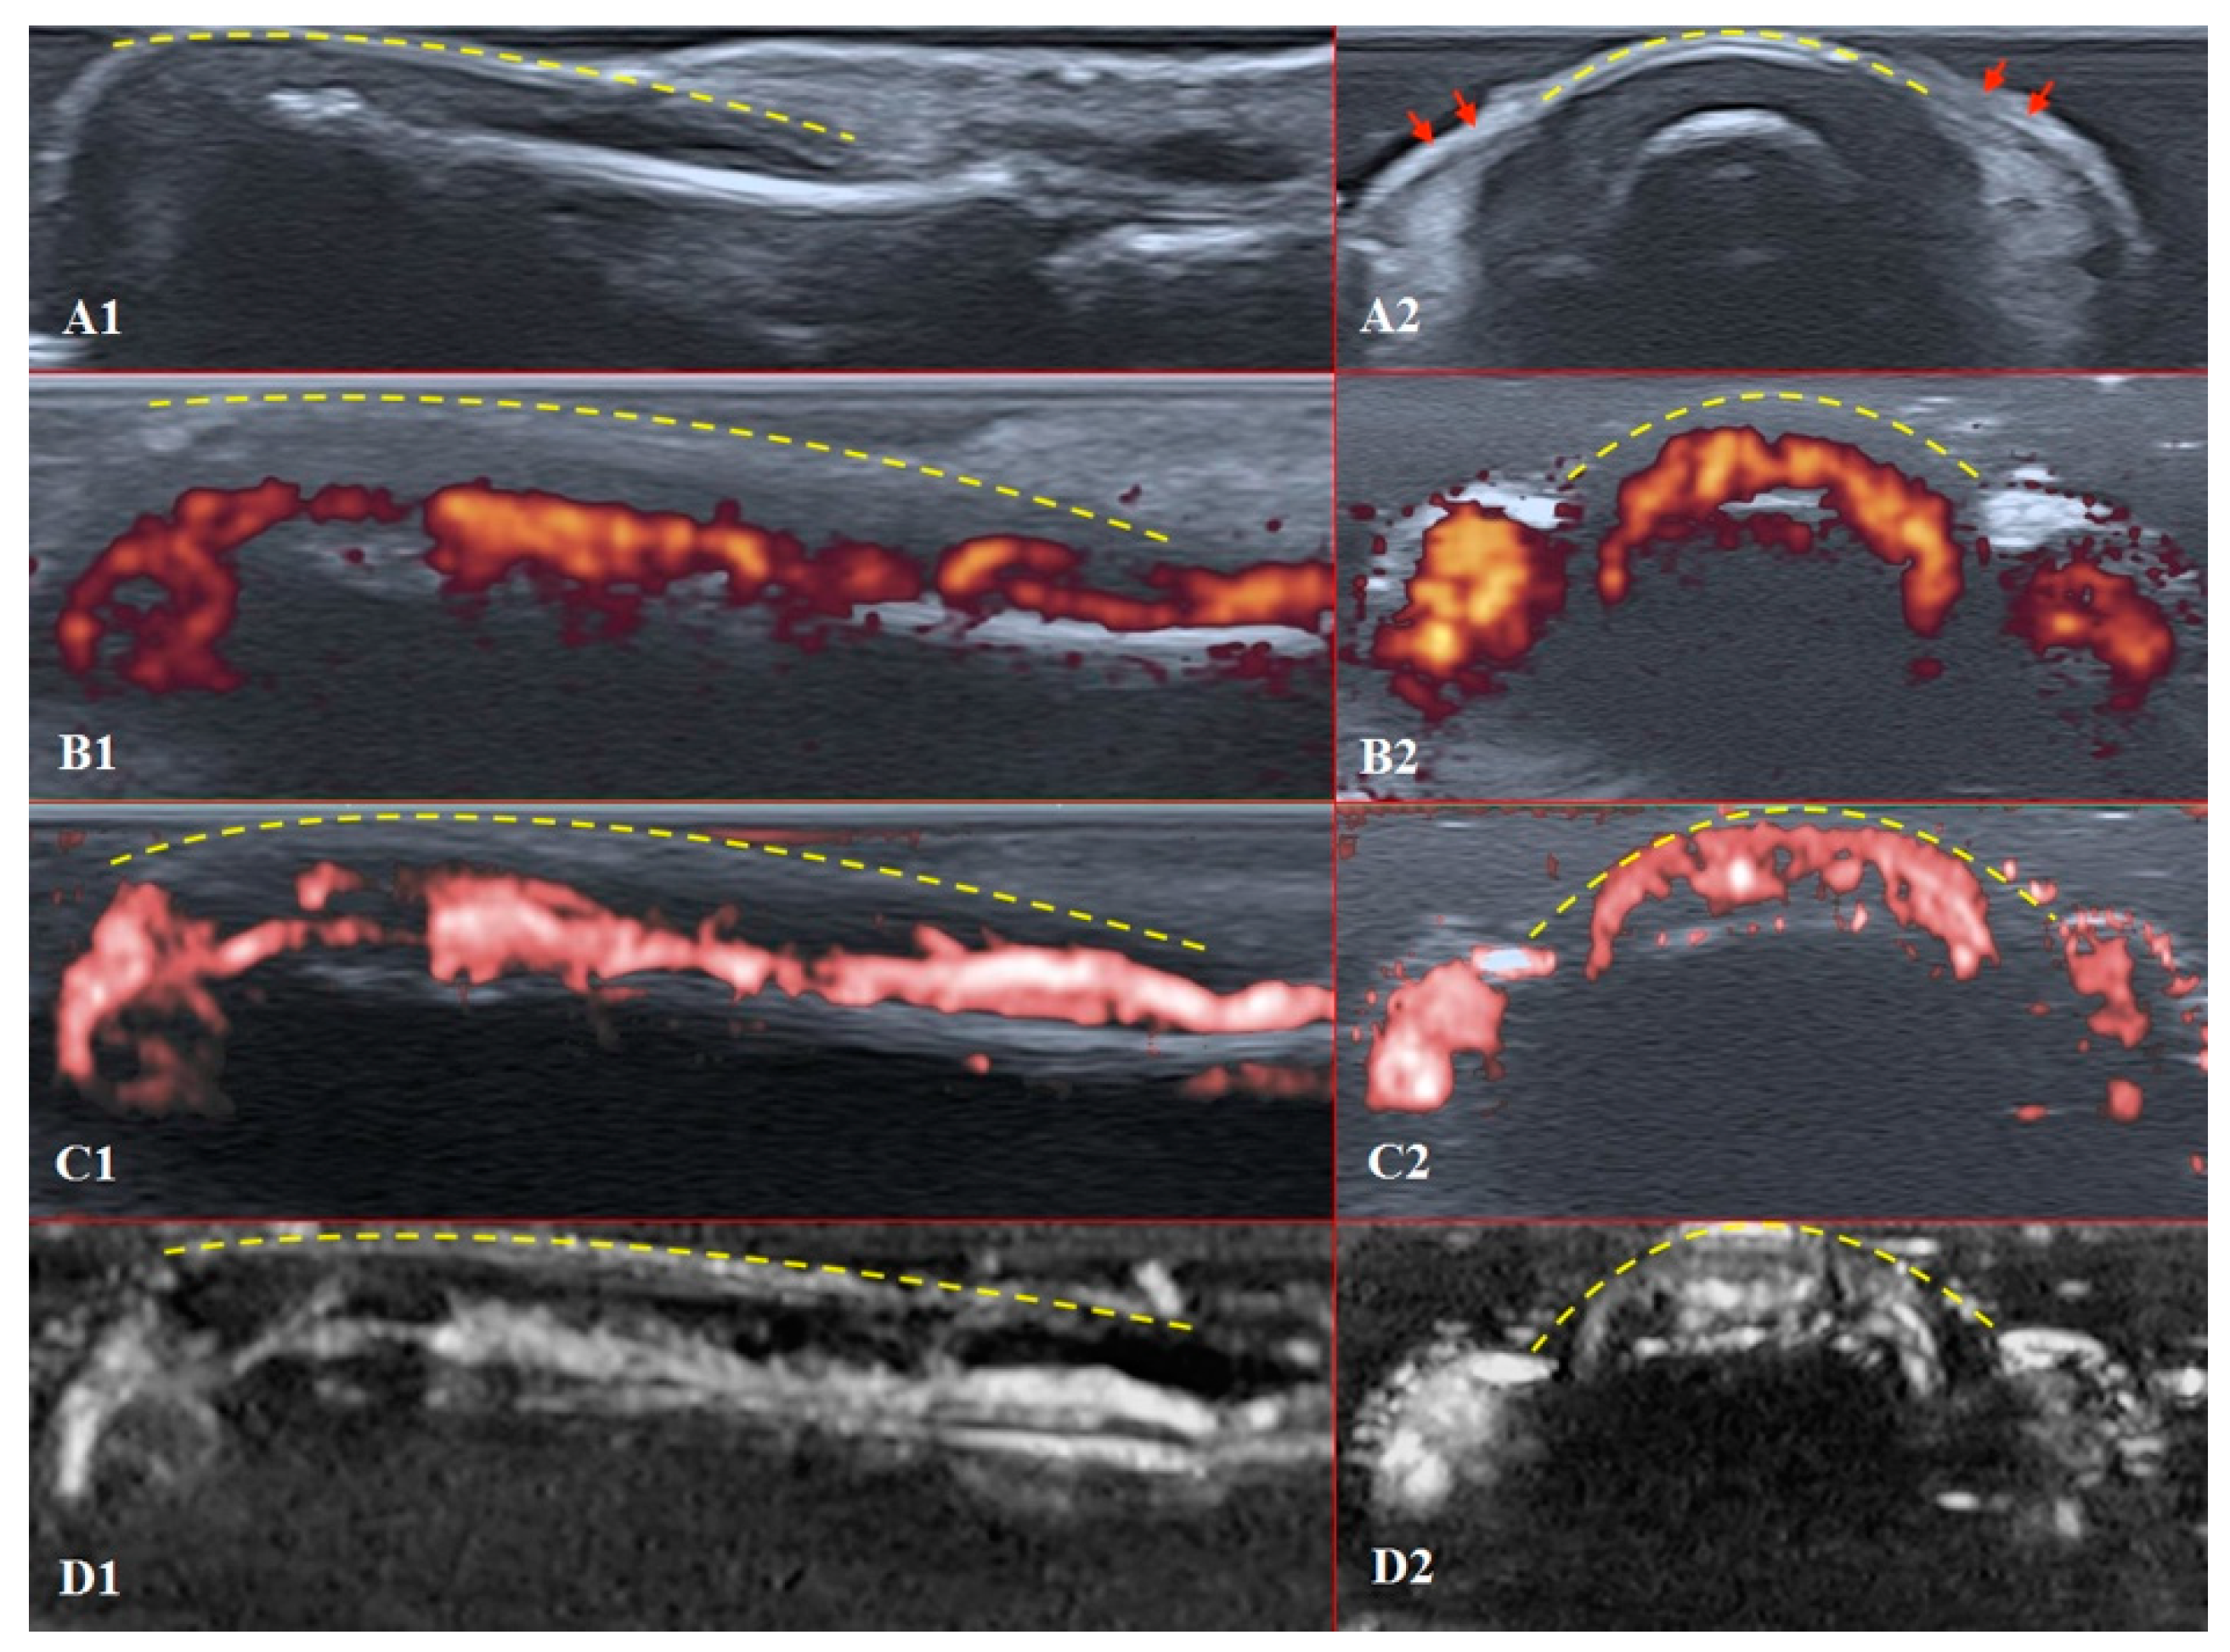

The structures of the nailfold are too small to assess by a conventional US. Thus, adequate sonographic evaluation is dependent on high-resolution techniques and high-frequency linear array probes. We used a diagnostic ultrasound system (CANON TUS-AI800, Canon medical systems Corp., Shimoishigami, Otawara-shi, JAPAN) equipped with a linear transducer with the following settings: 24 MHz ultrahigh-frequency (Canon medical systems Corp., Shimoishigami, Otawara-shi, JAPAN). Sagittal (dorsal volar) and transverse scans of fingertips were performed on a healthy volunteer (Figure 4) and a patient with late-course SSc (Figure 5). ROI was located between the fingernail and the bony surface of the distal phalanx. Up-to-date versions of SMI equipment provide a direct-control scale function. Therefore, the investigators do not need to worry about ROI.

PD and SMI settings have to be standardised for all evaluations. There is an appropriate option to differentiate primary Raynaud’s syndrome from its secondary development by setting the gain. Martinoli et al. suggested increasing the gain maximally and then slowly lowering it until the noise disappears and true signals remain [20]. Rubin offered a converse way to raise the gain manually until the colour box becomes filled with signals and a true flow is distinguished from the background as the next highest signal [21]. The method by Rubin seems to be a quick and comfortable technique to check vascularity in fingertip pulp and nailfold zones (Figure 6 and Figure 7). It takes less time to evaluate vascularity by SMI modes rather than the conventional PD technique due to its higher sensitivity for low flow. Monochrome SMI is a comfortable mode for the evaluation of vasculature and even vascular torsions, as the true flow has more power, and it is easier to separate these dots from the background of random noise artefacts (Figure 4D2).

The difference between healthy and SSc-affected fingertips is obvious using Rubin’s method. Higher gain shows that there is no signal in PD and minimal dots with both SMI modes (Figure 5).

Figure 4. Ultrasound images of the healthy fingertip of the second finger of a hand: (A1,A2) B mode/grayscale; (B1,B2) PD; (C1,C2) cSMI; (D1,D2) mSMI. The yellow dotted lines mark the nail. Sagittal scans (B1D1) in the midline of the fingertip show vascularity from the deep layers of the nailbed to the end of fingertip pulp. The main landmarks for all transverse scans (B2D2) are lateral nailfolds (A2 red arrows), which unite in the middle of the proximal nailfold and become a convex line.